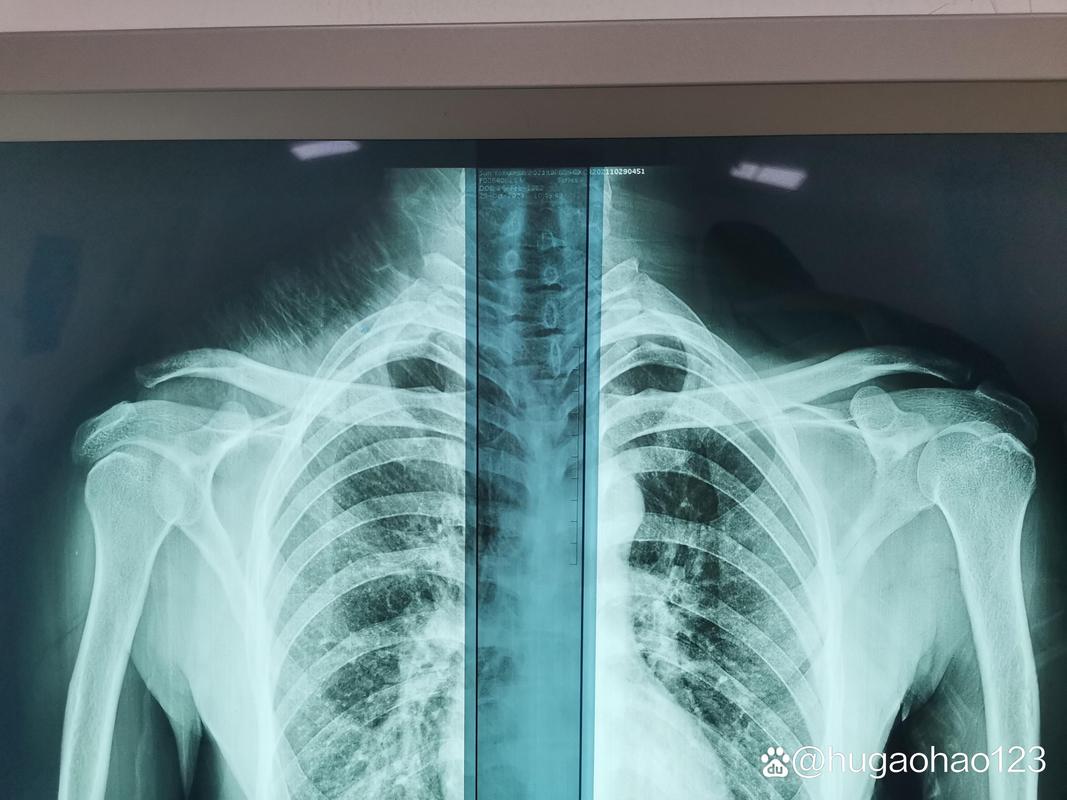

肩关节正位片是临床诊断中不可或缺的一环,它为医生提供了肩部骨骼与软组织的直观影像。拍摄这一影像并非简单的机械操作,而是需要患者与医护人员紧密配合的艺术。拍肩关节正位片究竟应该采取什么姿势呢?这看似简单的问题,实则蕴含着不少细节与讲究。

在探讨具体姿势之前,我们必须先理解为何肩关节正位体位如此重要。不同的体位会直接影响X光片的成像质量,进而影响医生的诊断。肩关节正位片主要用于评估骨折、脱位、关节炎等肩部疾病的状况,因此,每一个细节都关乎诊断的准确性。试想,如果患者因姿势不当导致影像模糊或失真,岂不是会让本就复杂的病情更加扑朔迷离?

拍肩关节正位片的标准姿势究竟是怎样的呢?通常情况下,患者需要面向X光机站立,双肩放松自然下垂。这一姿势看似简单,实则暗藏玄机。双肩放松是关键,如果患者因紧张而导致肌肉紧绷,肩部结构可能会发生微小变形,从而影响影像的准确性。手掌心可以向前或向内,确保肩膀正面充分暴露于X射线下。这一细节往往被忽视,但正是这些看似微小的调整,才能确保X光片能够全面反映肩部的真实情况。